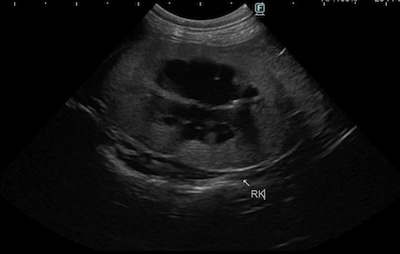

エコー検査より、両側の重度腎盂拡張、右腎臓の尿管拡張の所見が認められる。

右腎臓は6cm大に腫大、左腎臓は2cmに萎縮。

術前、術後のエコー比較